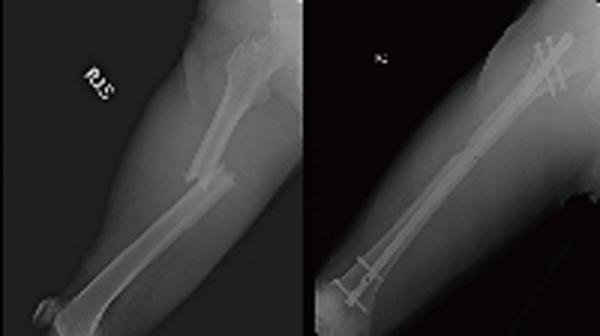

据台中光田综合医院昨天发出的文告,王先生送院诊断后,医生发现他有三根肋骨骨折、右腿股骨骨折、肝脏也有撕裂伤且腹腔出血。经外科、胸腔外科及骨科的共同治疗下,手术缝合额头伤口、股骨微创骨折复位固定,并给予输液、输血后病况稳定。